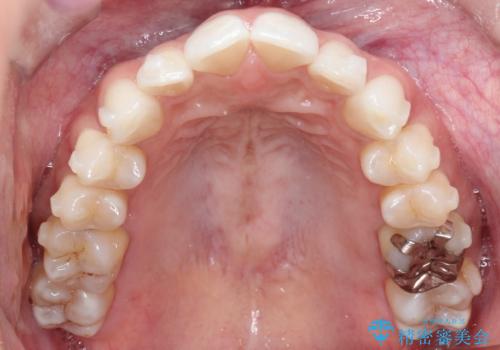

治療では、マウスピースの設計に基づき、奥歯から順に後ろへ移動させる遠心移動を行い、前歯のためのスペースを作りました。同時に、数箇所の歯の間にIPRを施すことで、歯の健康に影響のない範囲で精密に隙間を確保しました。

1年半の治療期間を経て、重なり合っていた前歯はスムーズに整列し、理想的なアーチ状の歯並びへと改善されました。抜歯を行わずに治療を完了したことで、噛み合わせのバランスを維持しながら、審美性を大きく向上させることができました。現在は保定期間に入り、美しい状態を維持されています。